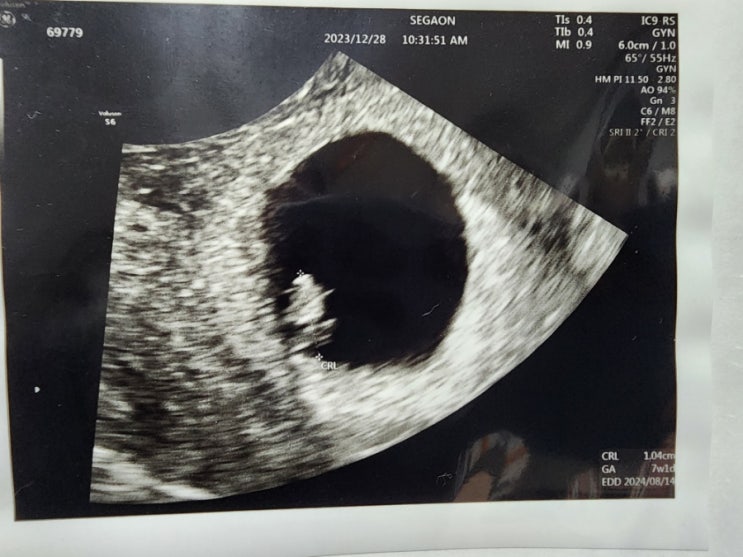

[임신 27주~29주] 근황과 태몽, 당근당근

다른 건 26주까지의 증상과 비슷한데 이제는 배를 살짝만 눌려도 괴롭다. 주차선이 좁게 그려진 주차장은 ...

[임신 24주~26주] 공포의 임당 검사 - 재검사

24주차였던 4월 말부터 26주차인 지금까지의 기록. 아래쪽 갈비뼈 쪽에 통증이 있다. 흉통이 넓어지는 느낌...

임신 23주까지의 기록

3월까지 편도 1시간 거리 장거리 출퇴근을 하다 보니 이게 임신해서 피곤한 것인가 아니면 갑자기 9 to 6 ...